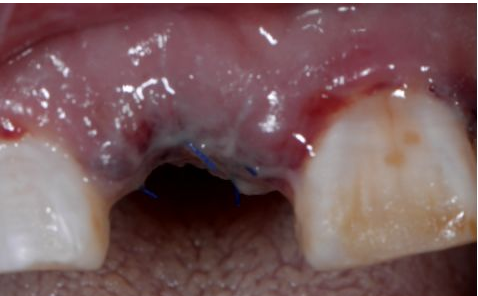

植入后縫合

術(shù)后三天

在口腔種植領(lǐng)域中,由于各種原因造成的種植牙局部牙槽突骨量不足或種植體周圍骨缺損的修復在種植外科的研究中已經(jīng)取得了重大突破。新一代的血漿提取物--濃縮生長因子(CGF,Concentrate Growth Factors)能夠明顯縮短術(shù)區(qū)成骨的時間,提高成骨質(zhì)量,促進成骨及組織的愈合;具體有:引導骨再生技術(shù)、聯(lián)合骨膜表面覆蓋加速軟組織愈合、用于上頜竇提升、拔牙后即刻種植、牙槽嵴位點保存、頜骨囊腫的治療、牙槽骨修整。